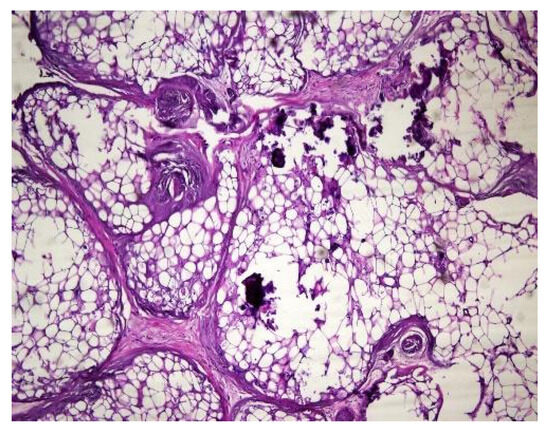

In both of the described cases, optical microscopy revealed lamellar fibrosis, deposits of fibrin on the surface of the peritoneum (Figure 3 and Figure 4) and dystrophic calcifications in the peritoneum (Figure 5 and Figure 6).

Several studies have attempted to identify and/or standardize the morpho-pathological changes in EPS, differentiating it from PS, which is a common occurrence in patients receiving PD and presents as a simple sclerosis [12,13,22,34,35]. The most frequent aspects observed were fibrin deposits, fibroblast swelling and mononuclear cell infiltration [11,12,22]. Garosi et al. investigated 39 biopsies from patients with EPS and found that tissue and arterial calcification, the thickening of the submesothelial layer and vasculopathy were the most significant observed changes [30]. In another study, Sherif et al. found that only fibrin deposits and the thickening of the compacta were significant [36]. In the present study, lamellar fibrosis, decreased cellularity, low grade perivascular inflammation and dystrophic peritoneal calcifications were frequent histological changes. Similarly, Braun et al. attempted to standardize the lesions and to define reproducible histological parameters in patients with EPS. It was found that calcification was a highly indicative criteria for EPS. Furthermore, mesothelial denudation, chronic inflammation, fibrin deposits, decreased cellularity and the presence of fibroblast-like cells were also indicative of EPS [10].

Figure 3. Lamellar fibrosis, condensed fibrin on the surface of the peritoneum and decreased cellularity (hematoxylin and eosin staining, original magnification × 100).

Jcm 13 02921 g003

Figure 4. Lamellar fibrosis, condensed fibrin on the surface of the peritoneum and decreased cellularity (hematoxylin and eosin staining, original magnification × 100).